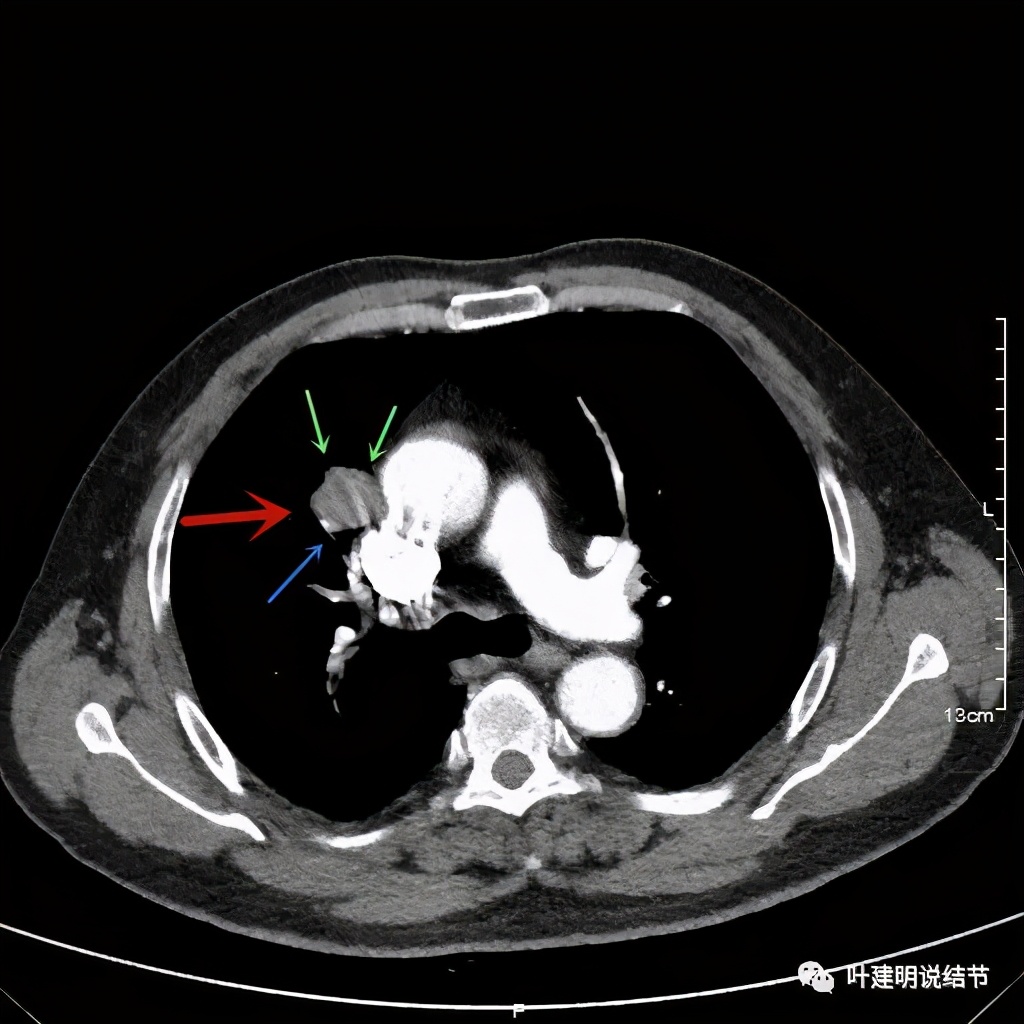

可见右上叶占位,我们现在知道了结果以后回头看,发现病灶的边缘在各个层面都是过于光滑(绿色箭头所示)。血管紧贴病灶边走行(桔色箭头所指),是不是有侵犯看不清楚,若是靶扫描加重建可能会更清楚点。支气管感觉也是贴着病灶走,但有的层面是不是截断,也不看的不太清楚。有的层面见局部有点状高密度(蓝色箭头所指),是不是错构瘤的局部钙化呢?若是纵隔窗又是如何?

上图示病灶密度不均

上图示病灶局部点状高密度(蓝色);边缘过于光滑(绿色)

上图示病灶密度不均,但边缘过于光滑(绿色);支气管似有截断(粉色);局部有点状钙化(蓝色)